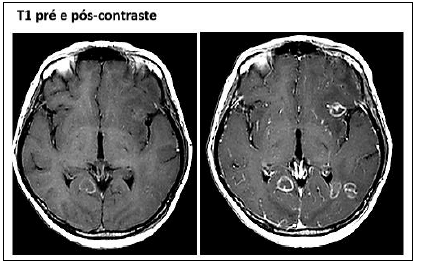

Paciente, 42 anos, sexo masculino, HIV positivo há quatro anos, em uso irregular de antirretrovirais no último ano. Devido a etilismo importante, foi levado por familiares ao hospital mais próximo de sua residência por causa do quadro iniciado há dois dias de cefaleia; rebaixamento do nível de consciência com confusão mental; sonolência; além de discreta perda de força do lado direito do corpo. O paciente realizou o seguinte exame de imagem na investigação do quadro:

Qual hipótese diagnóstica foi aventada?